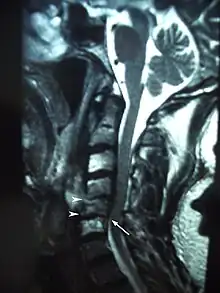

MRI showing osteoradionecrosis in the cervical vertebrae following radiotherapy for laryngeal cancer.